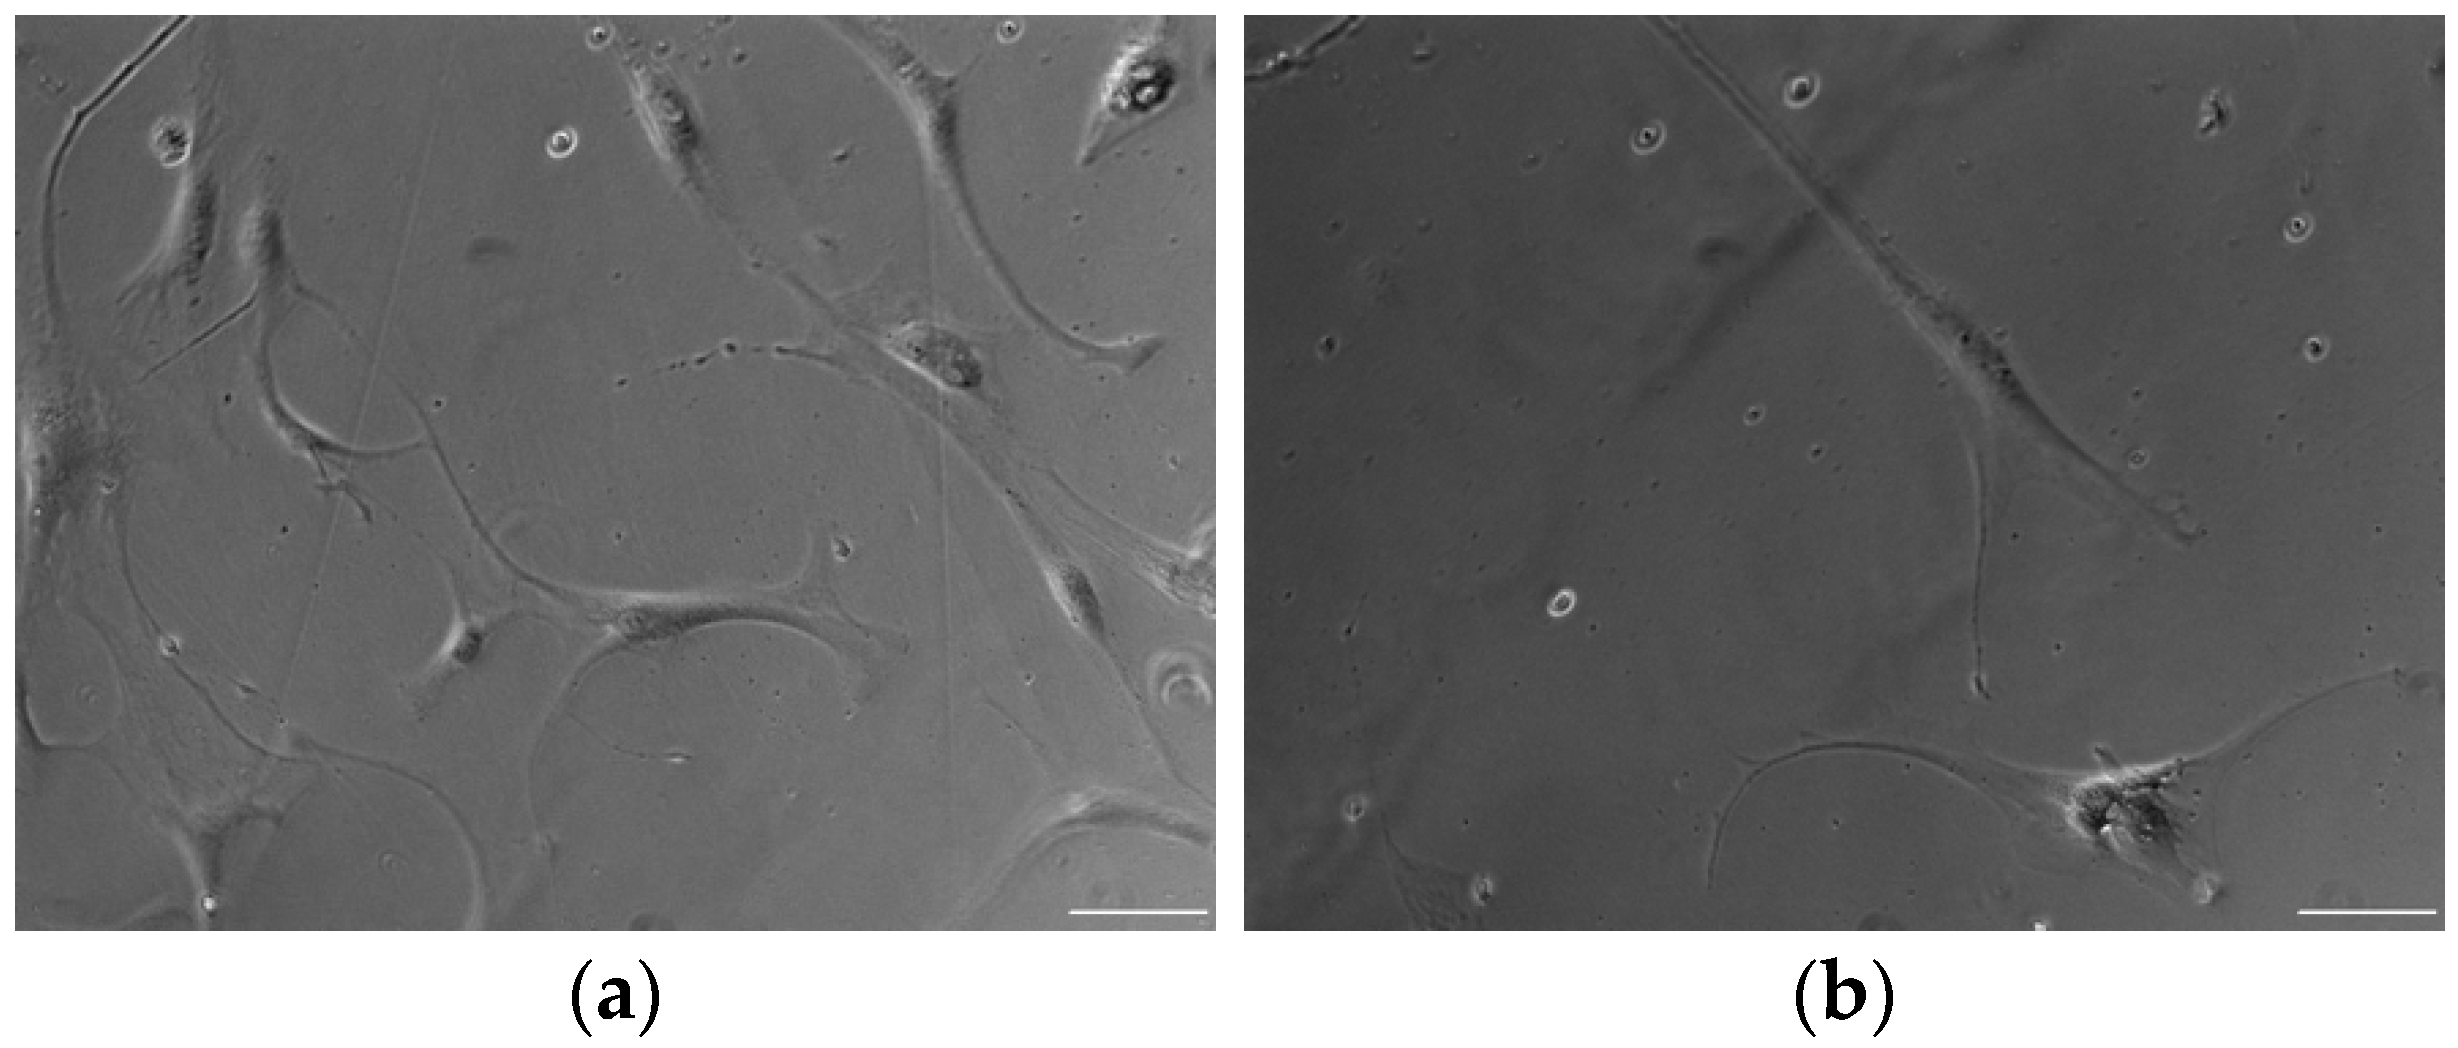

2.3. Cell Morphology

3.1. ADSC Morphology